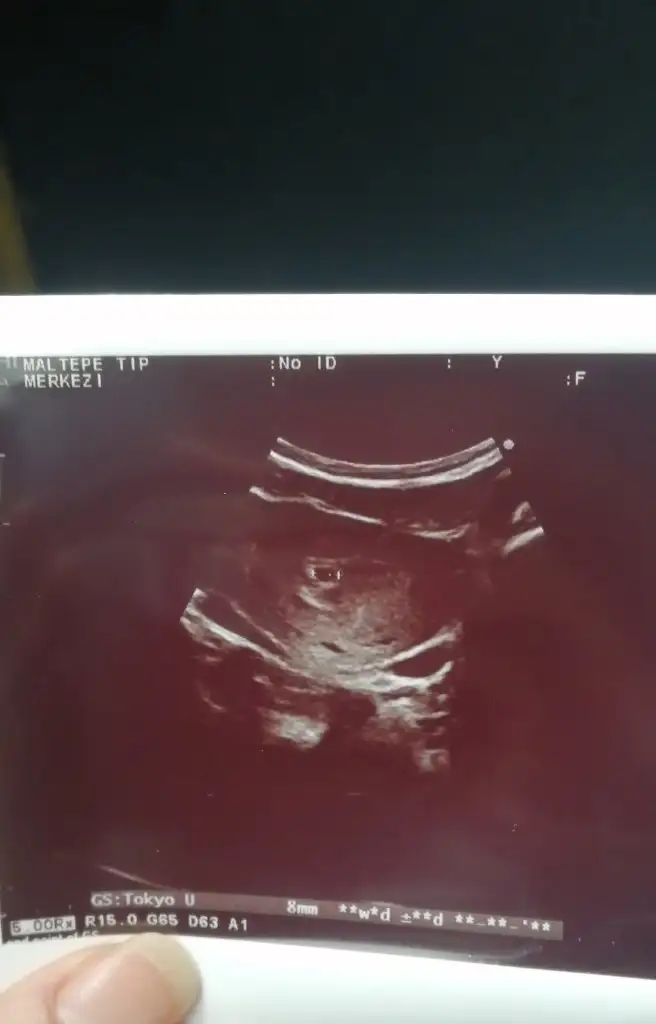

Geç döllenmedir canım senin beta nasıl ilerledi bugün verdin mi?Kızlaaar doktora gittik yeni çıktık sayılır ultrasonda üç haftalık falan gözüküyor kese net görülmedi birşey var ama kan da olabilir dedi doktor.. Aklıma takılan şey neden hesaba göre beşken ultrasonda üç hafta gözüküyor sizce

O zaman normal görememesi hatta yine iyi görmüş o küçük keseyi bende bir kaç gün önce gittiğimde hesabıma göre 4+6 dim karından hiç birsey göremedi hatta bir panik oldu alttan bakti hemen sonra güneş gibi doğdu kesem günümeMerhaba Hayır karından muayene etti

Makineler de fark ediyor bunu fark ettim, çoğu kişinin alttan görmüş doktorlar, benim de 4+6 randevum vardı kese için karından gördüO zaman normal görememesi hatta yine iyi görmüş o küçük keseyi bende bir kaç gün önce gittiğimde hesabıma göre 4+6 dim karından hiç birsey göremedi hatta bir panik oldu alttan bakti hemen sonra güneş gibi doğdu kesem günüme